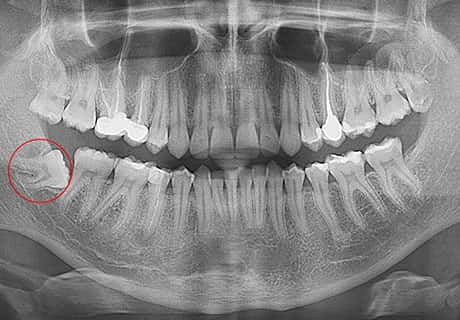

Атипичное расположение зуба